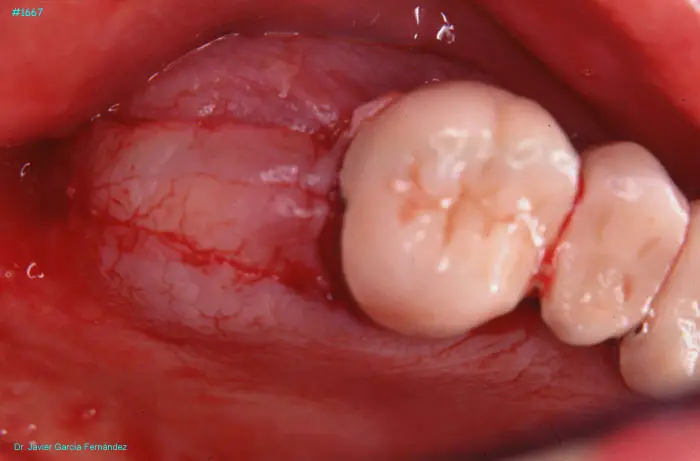

Atlas of Surgical Techniques in Periodontics. Chapter IV. Atlas de Técnicas Quirúrgica en Periodoncia

image 179